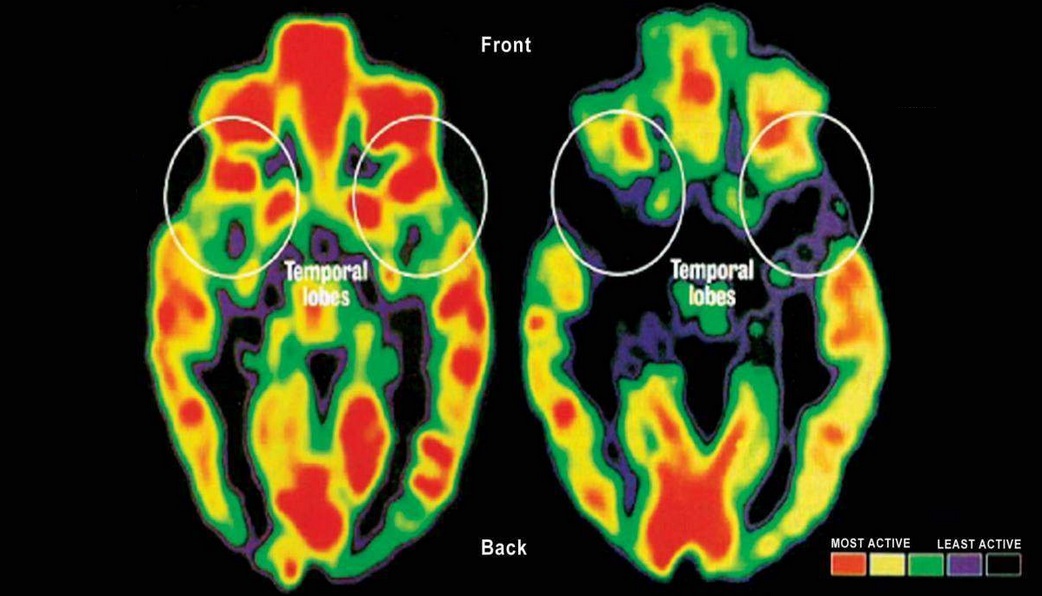

Hoje é comemorado o dia das crianças no Brasil, mas talvez o mundo não tem muito o que comemorar. Qual a diferença entre esses dois cérebros? Os dois são de crianças com a mesma idade. Mas por que o primeiro está muito mais vermelho e colorido? O vermelho significa massa cerebral e ativação neuronal. A diferença é que a criança da direita que tem um encéfalo menor e menos ativado vive na pobreza. Já é bem conhecido que a pobreza nos primeiros anos de vida está associada a baixo desempenho escolar, mas dois estudos publicados neste ano associaram a pobreza à diferenças no desenvolvimento da estrutura do cérebro. Crianças pobres tem um cérebro menor, que será menor para sempre, menos substância branca e cinzenta em áreas como o lobo temporal e lobo frontal, que são áreas do córtex cerebral, e o hipocampo. Estas áreas cerebrais, criticas para o raciocínio e necessárias para o sucesso acadêmico, são vulneráveis ao ambiente em que a criança se desenvolve. De acordo com a UNICEF, a pobreza cresce a cada ano no mundo e hoje uma a cada cinco crianças no mundo vive na pobreza. Uma intervenção política efetiva é urgente.